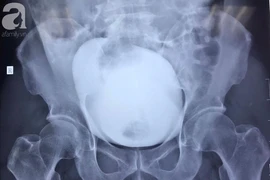

Sau một cú ngã tưởng chừng không quá nghiêm trọng, nam thanh niên 29 tuổi ở Sơn La phải nhập viện cấp cứu trong tình trạng vỡ bàng quang.

Nhịn tiểu khi uống bia, người đàn ông 46 tuổi bị vỡ bàng quang nguy hiểm, được các y bác sĩ Bệnh viện Nhân dân 115 cứu sống.